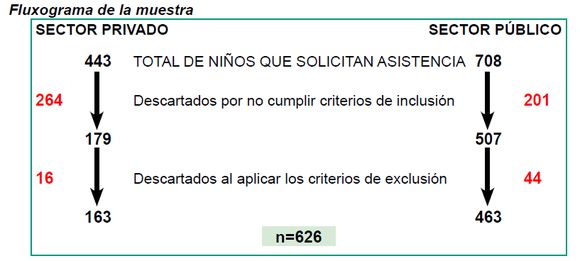

Diseño. Se diseñó un estudio transversal, observacional y descriptivo con el total de niños que solicitaron asistencia a: 1) la Cátedra de Odontopediatría de la Facultad de Odontología de la Universidad de la República entre julio y diciembre 2010; 2) dos consultorios privados en Montevideo, atendidos por Especialistas en Odontopediatría, integrantes del equipo.

Selección de la muestra. El estudio incluyó todos los niños y niñas nacidos entre los años 1993 y 2003, que solicitaron asistencia espontáneamente en los lugares citados y cumplieron los siguientes criterios de inclusión y exclusión:

Se evaluaron 626 niños (163 en el sector privado y 463 en la Facultad de Odontología) con una edad promedio de 10.82 ± 2.64. El valor de la prevalencia de MIH total fue de 11,82% (9.3-14.3).

En la tabla 1 se sintetizan los resultados de: prevalencia de MIH por tipo de cobertura, rangos etarios, media, desvío típico y distribución por sexo.

Los resultados intragrupo se representan en las Gráficas 1-6.

Prevalencia MIH según lugar de asistencia

Grupo 1 Sector Privado:

n=163 niños (41 se diagnosticaron con MIH),

Edad promedio 10.43 ± 2.79

La prevalencia de MIH fue de 25.2%. (Gráfica 1)

Grupo 2 Secor Público:

n=463 (33 se diagnosticaron con MIH)

Edad promedio 10.95 ± 2.59

La prevalencia de MIH fue de 7.13%. (Gráfica 2)